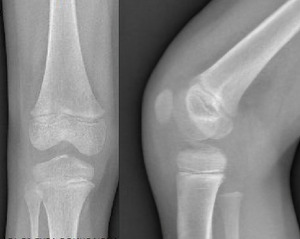

Plain anteroposterior and lateral radiographs demonstrated a bony fragment detached from the tibial plateau at the level of the tibial spine, consistent with a partially displaced, but not rotated, ACL avulsion fracture (Figure 1). The fracture was classified as a Type II Meyers and McKeever lesion based on radiographic features. Magnetic resonance imaging (MRI) confirmed the diagnosis, showing avulsion of the tibial spine with a fragment arising from the tibial eminence, associated bone marrow edema, and soft-tissue swelling. No meniscal tear or intermeniscal ligament entrapment, chondral lesion, collateral ligament injury, was detected (Figure 2).